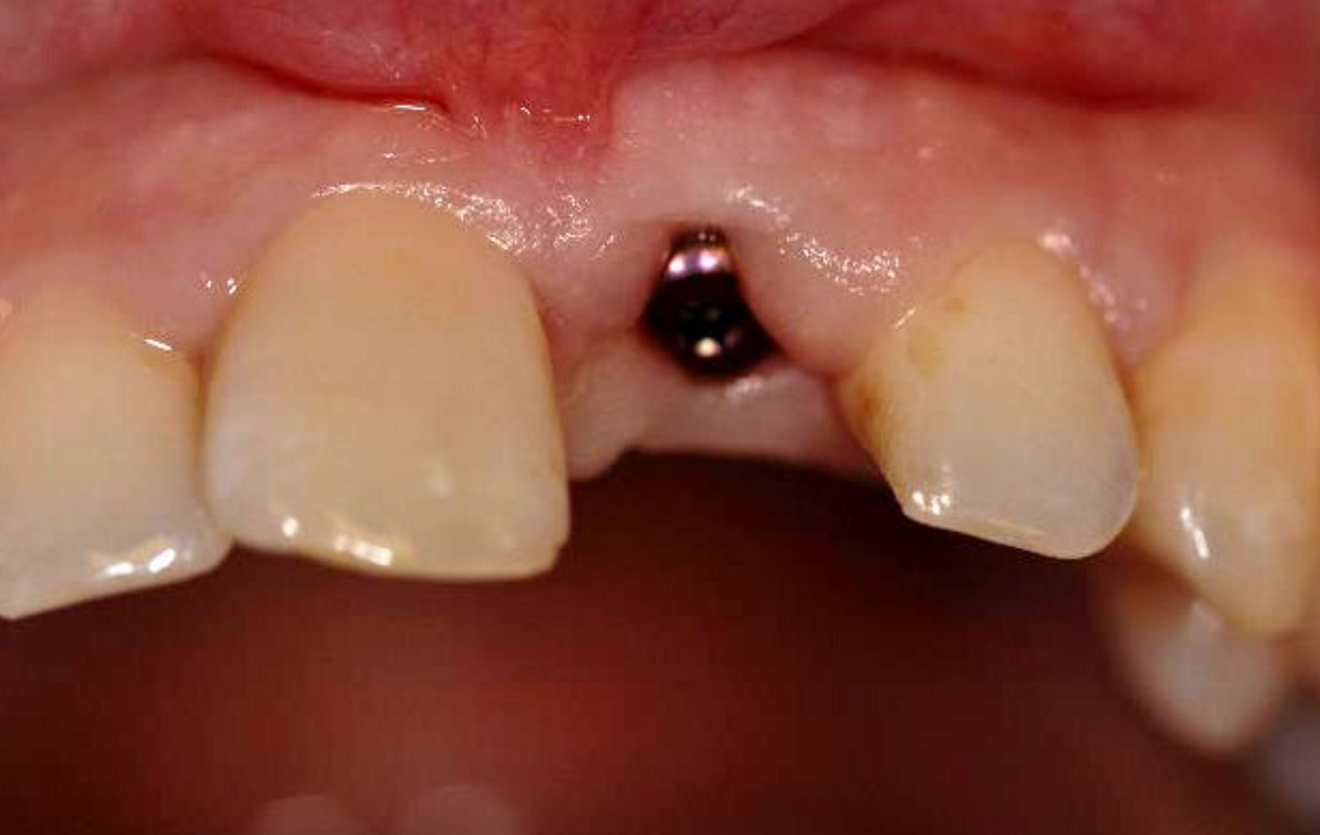

Figs. 2a–h: Demonstration of the study results through the case of a non-smoking 34-year-old female patient with a missing maxillary central incisor. Radiograph (a)...

...and clinical view at insertion of a narrow-platform 15 mm NobelActive implant (b).